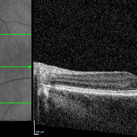

NIR and OCT Left Eye Early Parafoveal Changes Plaquenil

Jan 14 2025 by Kyle D Kovacs, MD

58 year old woman with 11 year history of plaquenil use with early parafoveal outer retinal attenuation and bull's eye on near-infrared imaging. Left eye

Condition/keywords: OCT, plaquenil toxicity